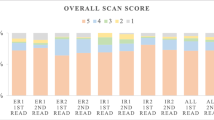

The overall number of definite focal assignments by SRS alone was 57% (50/87) for observer A and 61% (53/87) for observer B (Table 2). The attribution of foci to the liver achieved values of 98% (39/40) and 100% (40/40), respectively. Foci classified as pancreatic lesions were attributed in 62% (8/13) and 47% (7/13) of all cases, respectively. The assignment of foci to the gut attained values of 29% (2/7) and 43% (3/7), respectively. In the category “others”, definite assignments of 10% (1/10) and 30% (3/10), respectively, were observed. The assignment was poorest for mesenteric lymph nodes: 0% (0/17) and 6% (1/17), respectively.

Based on SRS/CT image fusion, definite assignments (Table 2) were made by observer A in 91% (79/87) and by observer B in 93% (81/87).

Image fusion increased the already high number of definite attributions as hepatic lesions to 100% (40/40) each. Furthermore, all (13/13) pancreatic lesions were now correctly classified by both observers. The greatest improvement due to image fusion was seen for the classification of abdominal foci as mesenteric lymph nodes. Their assignment was “definite” in 82% (14/17) and 94% (16/17), respectively. Moderate improvements were observed for the categories “gut” [71% (5/7) and 71% (5/7), respectively] and “others” [60% (6/10) and 70% (7/10), respectively]. The overall improvement was highly significant for both observer A (P<0.0001) and observer B (P<0.0001) using the exact Mantel-Haenszel test.

As Table 2 shows, there was an increase of foci classified as “definite” by both observers from 54% (47/87) to 86% (77/87) while the number of foci that could not be definitely classified by either observer dropped from 36% (31/87) to 5% (4/87). Furthermore, the percentage of discrepant observer results dropped from 10% (9/87) to 7% (6/87). According to two-factorial non-parametric analysis of longitudinal data (first factor: observer; second factor: method, i.e. no fusion vs fusion), there were no significant differences between the observers (in the mean of the methods: P=0.19500) and no interactions between observers and methods (P=0.79733), but highly significant differences between the methods (in the mean of the observers: P<0.0001).

Segmental assignment of liver foci

Table 1 shows the segmental assignment of 40 foci classified as hepatic lesions according to follow-up or postoperative histopathology. Segmental assignment of liver foci (n=40) based on SRS yielded definite assignments in 45% (18/40) for observer A and 58% (23/40) for observer B. The highest number of definite assignments was observed in case of segment VI: 80% (8/10) and 90% (9/10), respectively. The other foci were assigned as follows: segment IV, 45% (5/11) and 73% (8/11); segment V, 50% (1/2) and 0% (0/2); segment VII, 14% (1/7) and 14% (1/7); segment II, 50% (1/2) and 100% (2/2); and segment VIII, 25% (2/8) and 38% (3/8). There were no hepatic foci assigned to segments I and III.

The use of image fusion allowed definite segmental assignment of all hepatic lesions (40/40) in the case of observer B. Observer A assigned 98% (39/40) of all foci correctly, misclassifying a segment VIII focus as an extrahepatic lesion.

After image fusion, the number of hepatic foci classified as “definite” by both observers increased from 39% (14/40) to 98% (39/40). Consequently, the number of discrepant observer results (Table 3) was reduced from 31% (13/40) to 3% (1/40). Again, non-parametric multivariate analysis revealed no significant differences (P=0.10169) or interactions (P=0.28419) between the observers.